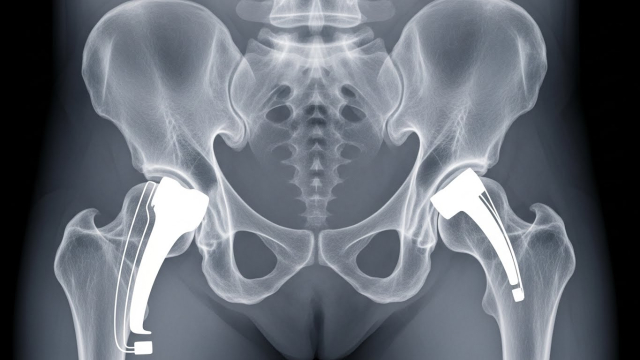

2) 무릎 vs 고관절, 비용 차이 포인트

같은 “인공관절”이라도 부위와 수술 난이도, 입원/재활 패턴이 달라서 총비용이 달라집니다. 특히 고관절은 골절/괴사 등 상황에 따라 입원·재활이 달라질 수 있어요.

상세 3) 무릎·고관절별로 비용이 달라지는 이유

무릎은 보행·계단·앉았다 일어날 때 통증이 심해 수술을 고민하는 경우가 많고, 고관절은 통증 위치가 사타구니/엉덩이 쪽으로 나타나 “허리 문제”로 착각하기도 합니다. 부위마다 수술 접근 방식과 회복 루틴이 달라져 비용 구조도 달라질 수 있어요.

• 무릎: 수술 후 초기 보행·근력 회복 중심 재활이 중요

• 고관절: 자세·보행 교정 + 낙상 위험 관리가 함께 중요